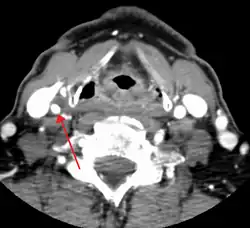

CT image of a 70 percent stenosis of the right internal carotid artery

One of several different imaging modalities, such as a computed tomography angiogram (CTA)[18][19][20] or magnetic resonance angiogram (MRA) may be useful. Each imaging modality has its advantages and disadvantages - Magnetic resonance angiography and CT angiography with contrast is contraindicated in patients with chronic kidney disease, catheter angiography has a 0.5% to 1.0% risk of stroke, MI, arterial injury or retroperitoneal bleeding. The investigation chosen will depend on the clinical question and the imaging expertise, experience and equipment available.[21]